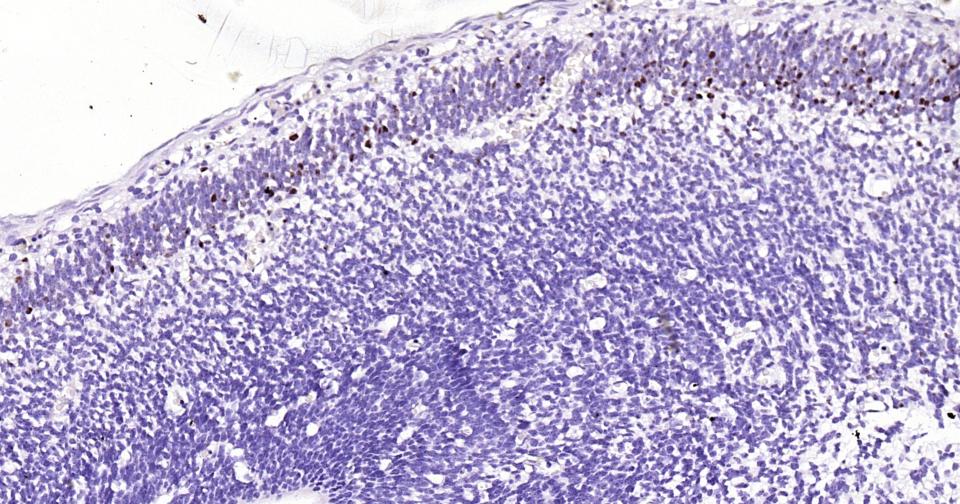

IHC-PHuman, Mouse, Rat1:100-500

组织特异性

Brain.